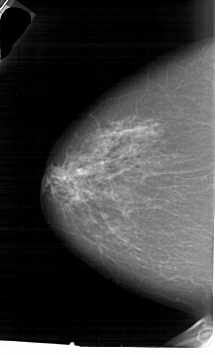

A_1646_1.LEFT_MLO

LEFT_MLO LINES 6871 PIXELS_PER_LINE 3751 BITS_PER_PIXEL 12 RESOLUTION 43.5 NON_OVERLAY